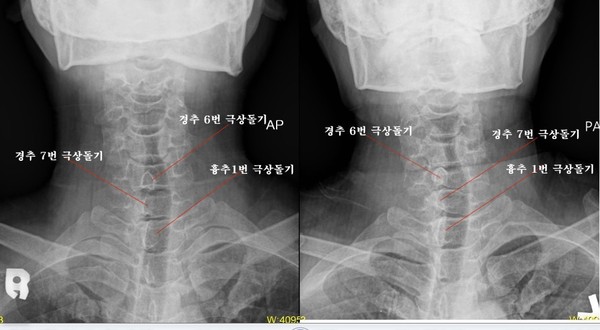

이날 감정위원들은 14개의 감정항목을 결정했다. 이 가운데는, 주신씨 명의 엑스레이 사진에서 볼 수 있는 흉추1번-경추7번 극상돌기 배열방향의 차이, 흉곽의 비율 등이 포함돼 있다.

- ▲ 최대집 의혁투 공동대표가, 엑스레이 촬영위치 및 각도의 차이에 따라 극상돌기의 방향이 다르게 보일 수 있는 지를 확인하기 위해 실험한 엑스레이 사진. 왼쪽은 AP(전-후면 사진), 오른쪽은 PA(후-전면 사진). ⓒ 최대집 대표 제공.

‘극상돌기’의 경우에도 차이점은 명확히 드러난다.

변호인 측은 “공군에서 찍은 엑스레이와 비자발급을 위해 찍은 엑스레이에서는 피사체의 제 1흉추 극상돌기가 오른쪽으로 휘어있지만, 자생병원에서 찍은 영상에서는 정방향으로 나온다”며, “박주신씨가 공군에 입대해 찍은 엑스레이와 세브란스 공개신검에서 나타난 피사체의 의학적 차이가 명확해 동일인이라고 인정할 수 없다”고 지적했다.

우리가 흔히 등을 만지면, 가운데 뾰족하게 솟아난 부분이 바로 ‘극상돌기’다.

흉추를 비롯해 모든 척추에 존재하며, 흉추에 외상이나 수술, 질병 등이 없었던 근접한 기간 동안 촬영된 엑스레이에서, 극상돌기의 형태가 명확하게 다를 경우, 다른 개체라고 판단할 의학적 근거가 된다.